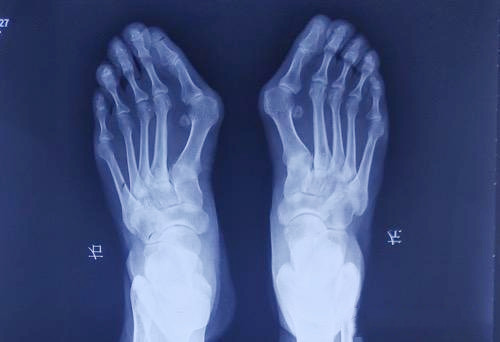

大脚趾外翻是一种常见的足部问题,主要表现为大脚趾向外侧偏斜,超过正常生理角度15度以上。这种情况不仅会影响脚部美观,更重要的是会对日常行走造成困扰。当大脚趾向外翻时,往往会挤压旁边的其他脚趾,导致它们也出现不同程度的变形。同时,大脚趾近端的趾骨头会向内突出,使第一跖骨基部变得明显。在走路时,突出的部位很容易与鞋子发生摩擦,特别是鞋子前部较窄的情况下,这种摩擦会加剧,导致滑液囊发炎,形成厚厚的茧子,让人感到疼痛不适。